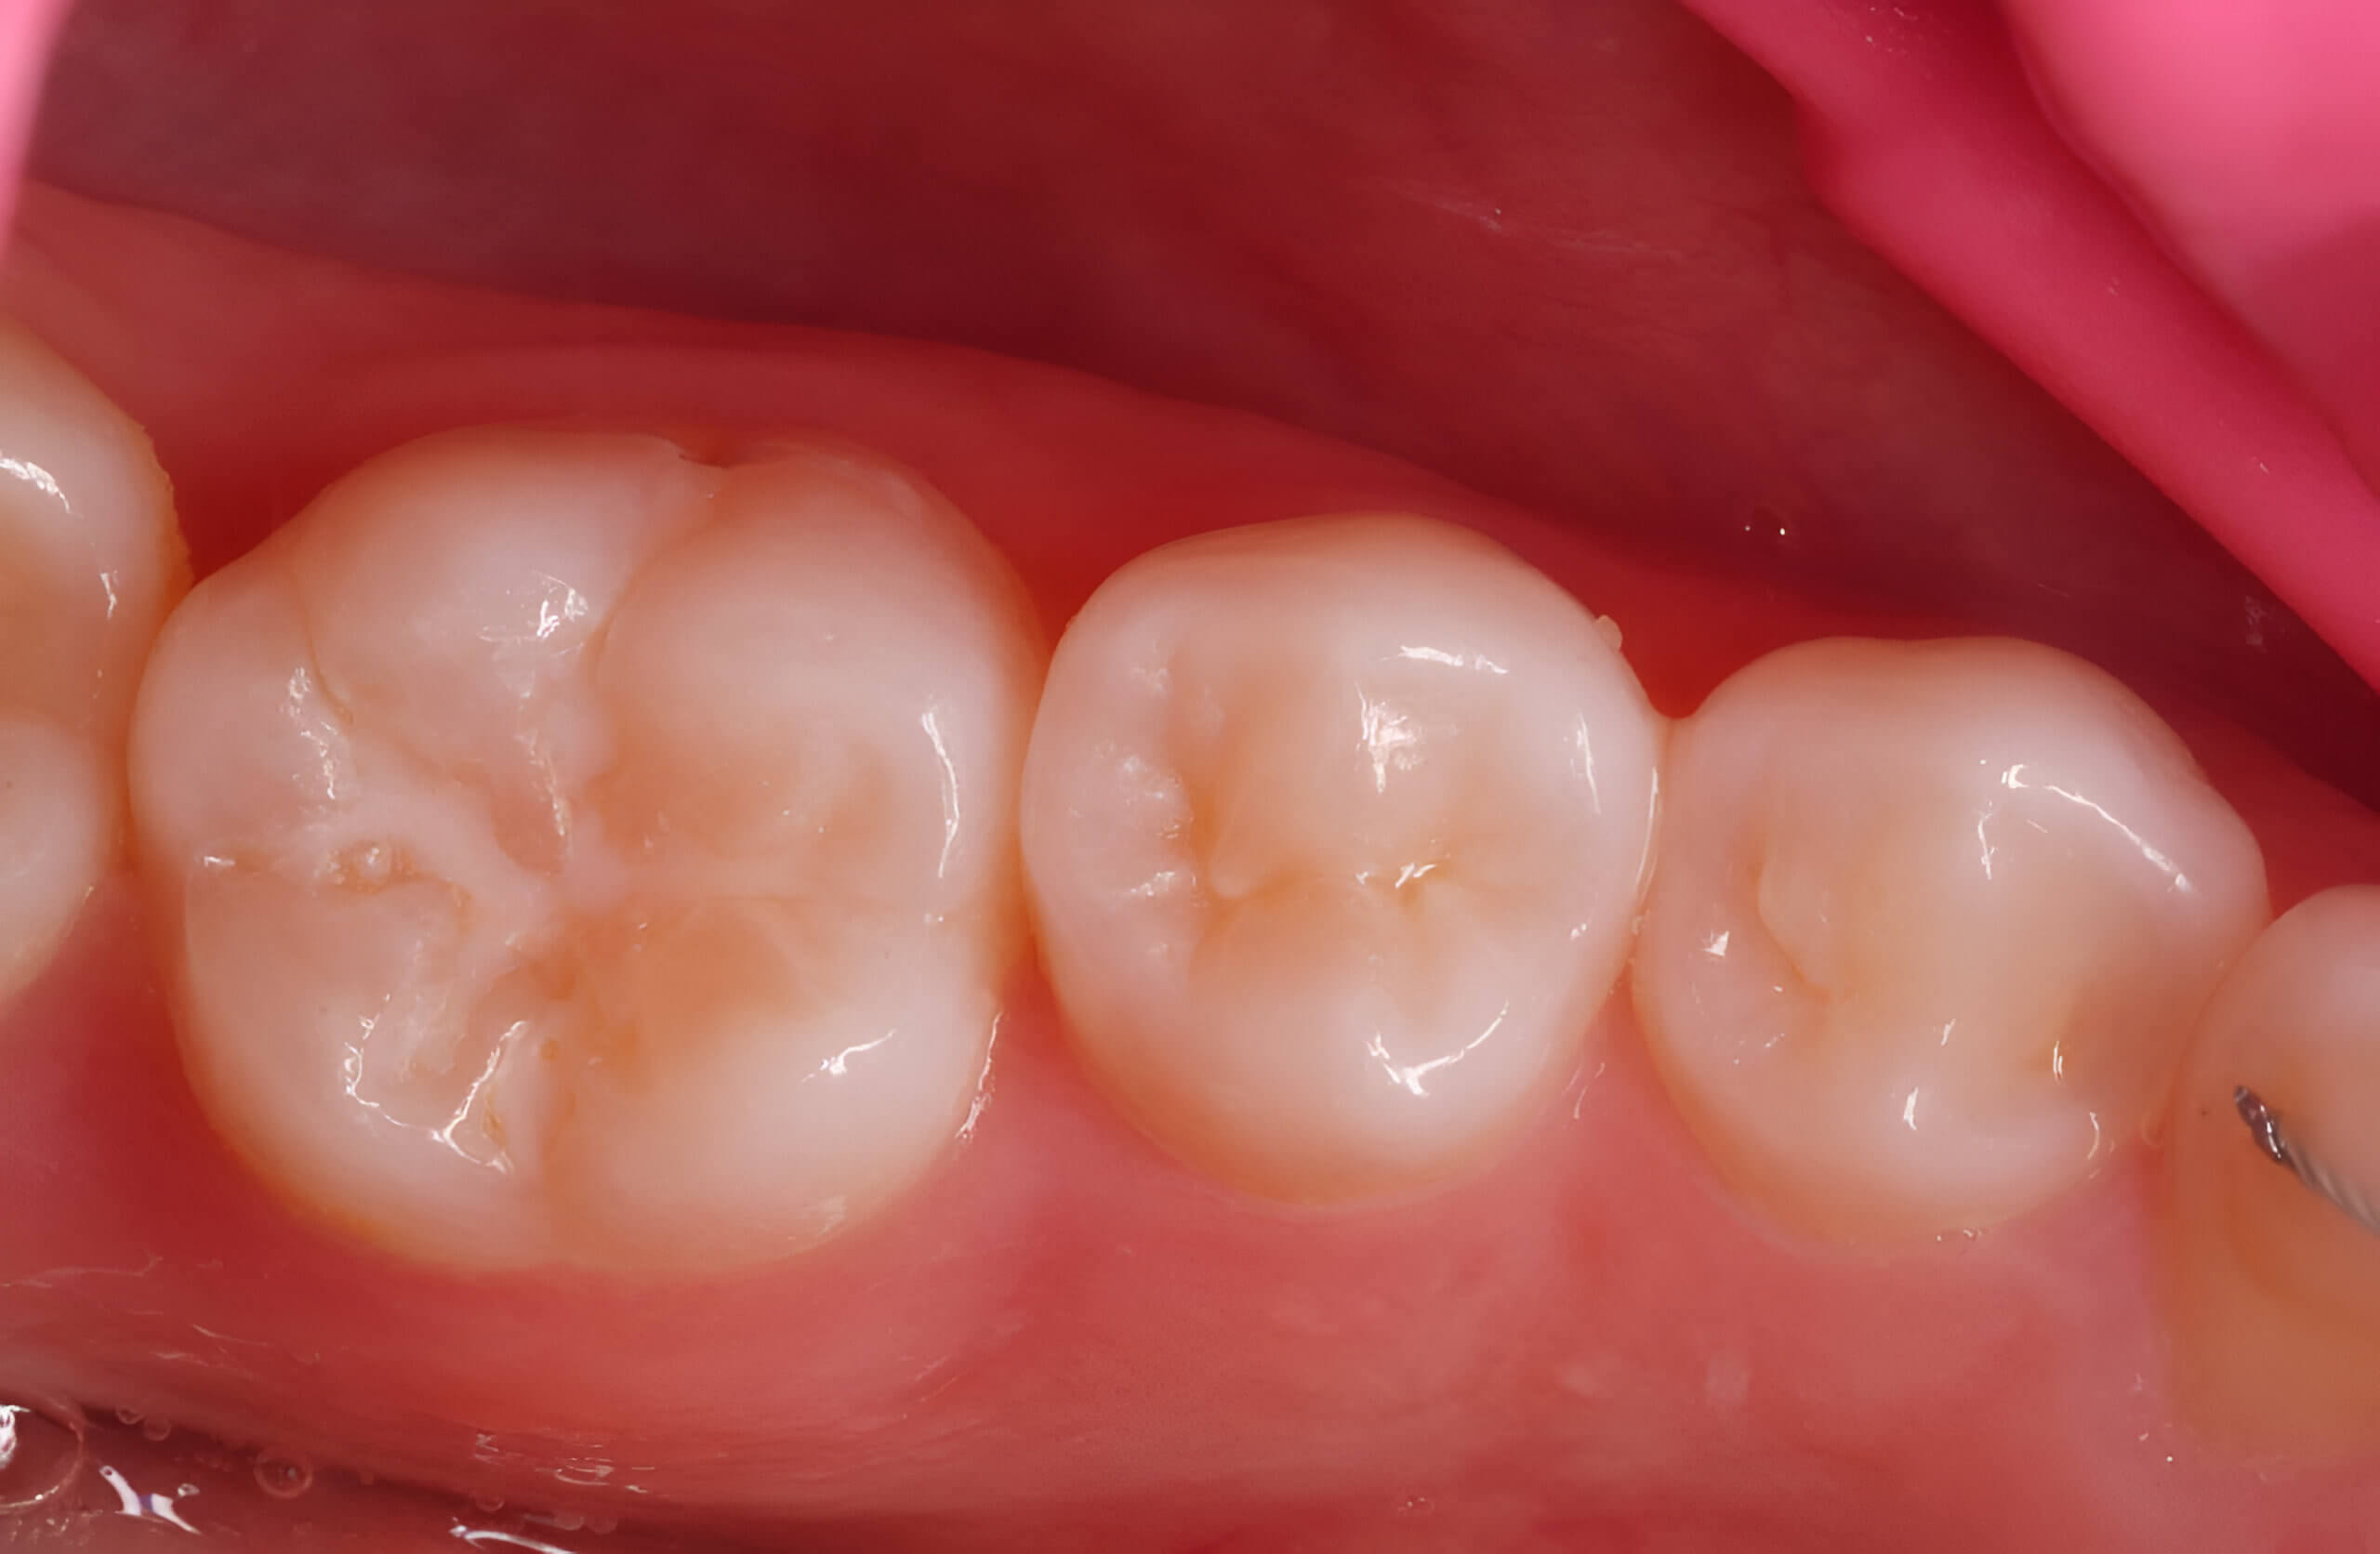

3. Post-operative view of the restoration after contouring. Stain application: BROWN by G-White in the fissure area to mimic pigmented fissures. (Images 3, 4)